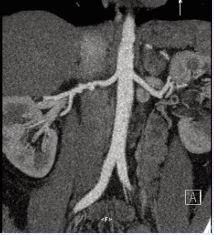

Her chest X-ray and ECG were normal. During the echocardiography investigation, a slight hypertrophy of the ventricular walls was described, without any impact on the overall and segmented heart function and no hemodynamically significant valvulopathy.We started her on standard anti-hypertensive medications with combination of calcium channel blocker and angiotensin receptor blocker and did further investigations. As renal artery stenosis was suspected from clinical examination, renal Doppler was performed, which did not reveal any renal artery stenosis. Because of low sensitivity of the renal Doppler examination, arterial stenosis was not ruled out. Since clinical examination and different kidney sizes were in favor of renal artery stenosis, we decided to go for CT renal angiography which revealed multifocal renal FMD in right renal artery with angiographic appearance of strings of beads (Figure 2). Left renal artery was normal.

Figure 2: CT renal angiography which revealed multifocal renal FMD in right renal artery with angiographic appearance of strings of beads with normal left renal artery.